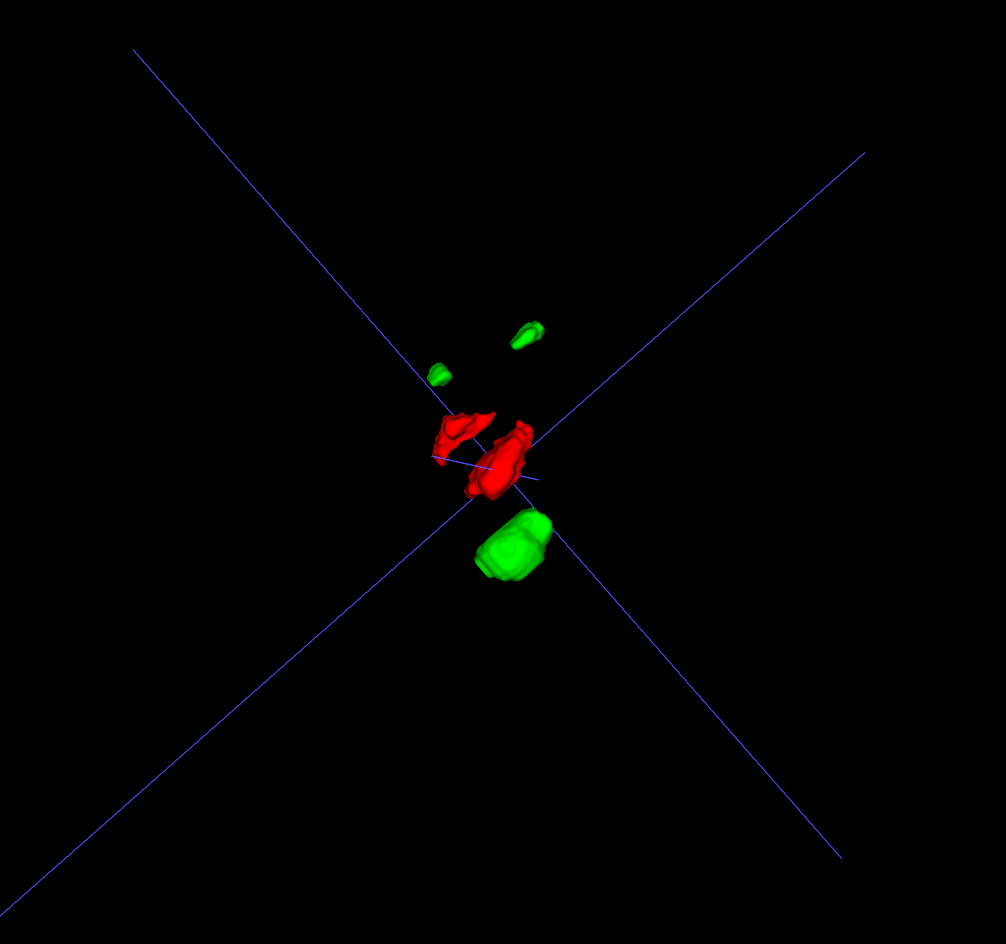

Head and neck tumor segmentation challenge (HECKTOR) provides an opportunity for researchers to develop 3D algorithms for the segmentation of H&N primary tumors (GTVp) in 3D PET/CT scans. HECKTOR 2022 [2, 5] is a third edition of the challenge which consists of 883 cases (524 labeled cases were provided for training), each with 3D CT, 3D PET rigidly registered to a common frame, but at different resolutions. The ground truth 3D labels provide dense 3D annotations of 2 structures: gross tumor volumes of the primary tumors (GTVp) and lymph nodes (GTVn). Generally PET images highlight tumor activity at a lower resolution, whereas CT images provide higher resolution anatomical details. In case of the radiotherapy treatment, the tumor delineation must be done in the CT coordinate system, which which will be used to calculate the radiation dose to the tumor region. The HECKTOR22 challenge also includes the second task of outcome prediction, but here we focus solely on the segmentation task. The data used in this challenge comes from multiple institutions (9 centers in total), including 4 centers in Canada, 2 centers in Switzerland, 2 centers in France, and 1 center in the United States for a total of 883 patients with annotated GTVp and GTVn [2, 5].

The ground truth labels usually include a single mass of the primary tumor (but in some cases it was absent completely or had two components), and several connected components of the annotated lymph nodes. An example case of CT and the corresponding PET image with ground-truth overlays is shown in Figures 1 and 2.